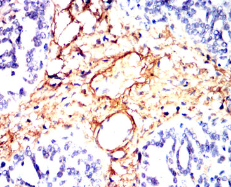

COL2A1 Mouse Monoclonal antibody[7F2A1]

IHC    1/200 - 1/1000